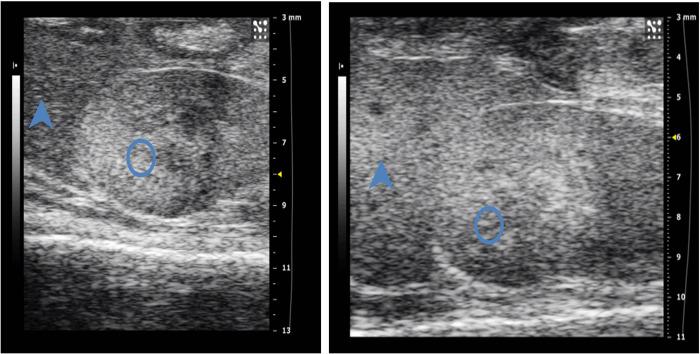

Inflammatory bowel disease (IBD) and atherosclerosis (AS) are both common chronic inflammatory diseases with similar pathophysiological mechanisms. Some studies have shown that IBD patients are at increased risk for early atherosclerosis, myocardial infarction and venous thrombosis. Here we set up a hybrid mouse model associated with atherosclerosis and acute colitis in order to investigate the interplay of the two diseases. We fed ApoE-/- mice with high fat diet to establish atherosclerosis model, and used animal ultrasound machine to detect the artery of mice noninvasively. Then a new hybrid model of atherosclerosis and acute colitis was prepared by drinking water for 7 days. At the end of the experiment, the hybrid model mice showed typically pathological and intuitionistic changes of atherosclerosis and acute colitis. We found the shortened colon length, high histopathological scores of the colon with mucosal erosion and necrosis, hyperlipidemia, a plaque-covered mouse aorta and plaque with foam cells and lipid deposition in the hybrid model group, which proved that the hybrid model was successfully established. At the same time, ultrasonic detection showed that the end-diastolic blood flow velocity and the relative dilation value were decreased, while systolic time / diastolic time, the wall thickness, systolic diameters as well as diastolic diameters were gradually increased, and statistical significance appeared as early as 8 weeks. We clearly described the process of establishing a hybrid model of atherosclerosis and acute colitis, which might provide a repeatable platform for the interaction mechanism exploring and drug screening of atherosclerosis and inflammatory bowel disease in preclinical study.

炎症性肠病(IBD)和动脉粥样硬化(AS)都是常见的慢性炎症性疾病,具有相似的病理生理机制。一些研究表明,IBD 患者发生早发动脉粥样硬化、心肌梗死和静脉血栓形成的风险增加。在这里,我们建立了一个与动脉粥样硬化和急性结肠炎相关的杂交小鼠模型,以研究这两种疾病的相互作用。我们用高脂肪饮食喂养 ApoE-/- 小鼠以建立动脉粥样硬化模型,并使用动物超声机对小鼠的动脉进行非侵入性检测。然后,通过连续 7 天饮水建立了新的动脉粥样硬化和急性结肠炎杂交模型。实验结束时,杂交模型小鼠表现出典型的动脉粥样硬化和急性结肠炎的病理和直观变化。我们发现,杂交模型组小鼠的结肠缩短,结肠黏膜糜烂和坏死的组织学评分较高,存在高脂血症、斑块覆盖的小鼠主动脉以及斑块中泡沫细胞和脂质沉积,证明该杂交模型成功建立。同时,超声检测显示,舒张末期血流速度和相对扩张值降低,而收缩时间/舒张时间、壁厚度、收缩直径以及舒张直径逐渐增加,早在 8 周时就出现了统计学意义。我们清楚地描述了建立动脉粥样硬化和急性结肠炎杂交模型的过程,为临床前研究中动脉粥样硬化和炎症性肠病的相互作用机制探索和药物筛选提供了一个可重复的平台。